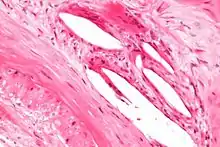

Internal elastic lamina

The internal elastic lamina or internal elastic lamella is a layer of elastic tissue that forms the outermost part of the tunica intima of blood vessels. It separates tunica intima from tunica media.

It is readily visualized with light microscopy in sections of muscular arteries, where it is thick and prominent, and arterioles, where it is slightly less prominent and often incomplete.[1] It is very thin in veins and venules.[1] In elastic arteries such as the aorta, which have very regular elastic laminae between layers of smooth muscle cells in their tunica media, the internal elastic lamina is approximately the same thickness as the other elastic laminae that are normally present.[2]

There is small amount of subendothelial connective tissue between basement membrane of endothelial cells and internal elastic lamina.[3]

Reduplication of internal elastic lamina can be seen in elderly individuals due to intimal fibroplasia, which is part of the aging process.[4]